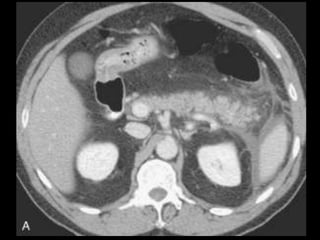

Pancreatite Crônica

TC: dilatação e estreitamentos ductais irregulares,

atrofia do parênquima e calcificações pancreáticas;

Dilatação é frequente, mas não é específica:

carcinomas pancreáticos e ampulares;

Um ducto uniforme e dilatado, com uma razão do

diâmetro do ducto para o diâmetro total da

glândula superior a 0,5 é sugestivo de carcinoma.

Cálculos ou calcificações pancreáticas são as

manifestações na TC mais específicas da PC e não

se encontram em associação à obstrução

neoplásica.

Embora a história clínica, calcificações na massa,

cálculos ductais e ramos laterais ductais dilatados

possam ajudar a diferenciar as massas benignas

das malignas, isso pode não ocorrer sempre,

porque uma pancreatite obstrutiva aguda e crônica

pode preceder um carcinoma demonstrável;